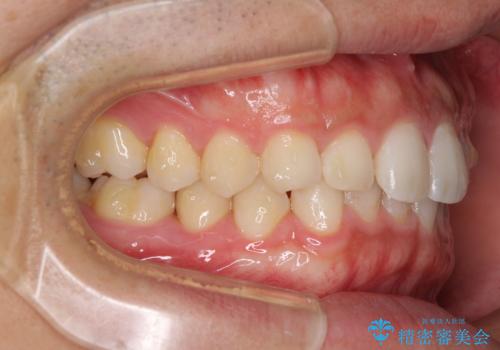

細かい隙間にものがはさまる インビザラインによる矯正治療

- 上下の前歯の隙間を気にして来院された患者様です。

インビザラインを用い、上下歯列のスペースを閉じていくこととしました。